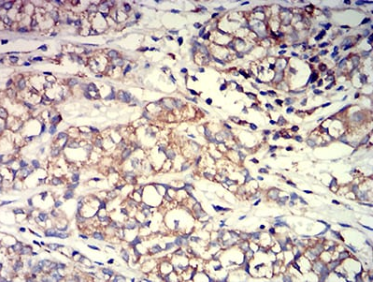

IHC    1/200 - 1/1000